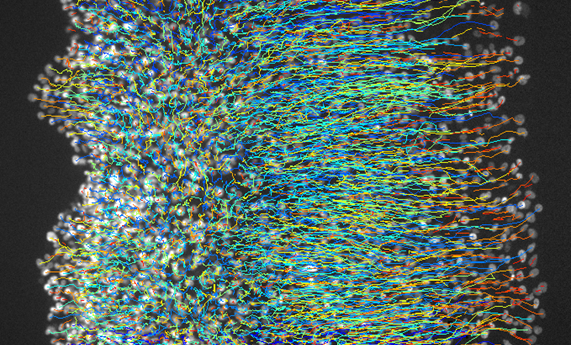

Las células se mueven en grupo hacia tejidos rígidos